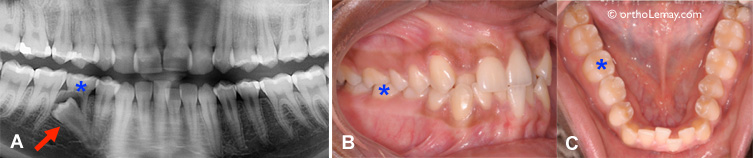

(A, B, C) Cet autre exemple montre une situation d’éruption ectopique de la seconde prémolaire inférieure droite (flèche) qui aurait pu être évitée par l’extraction de la molaire temporaire (* bleu) et la pose d’un mainteneur d’espace pendant l’éruption. Cette fille de 17 ans a maintenant toutes ses dents en bouche sauf la prémolaire incluse et mal positionnée.

À l’opposé, comme l’illustre l’exemple suivant, l’espace de dérive inférieur droit a été perdu lorsque la deuxième molaire temporaire a été extraite et qu’aucun mainteneur d’espace n’a été utilisé pour empêcher la migration des dents. La prémolaire (*) se trouve bloquée par les dents qui ont basculé de part et d’autre de l’espace d’extraction.